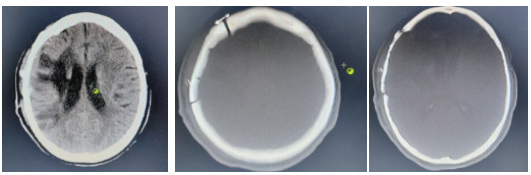

术后复查头颅CT

2024年12月31日 ,胡女士再次返院进行修补缺损颅骨手术治疗。入院后完善相关术前准备,2025年1月7日,在陆军军医大学第一附属医院(西南医院)专家薛兴森副主任医师指导下,我院神经外科团队成功为胡女士完成颅骨缺损自体骨瓣修补术。术后,患者在神经外科医护团队密切监测和精心照护下,整个围手术期未出现发热及伤口感染等并发症,患者及家属对治疗效果非常满意,现已康复出院。